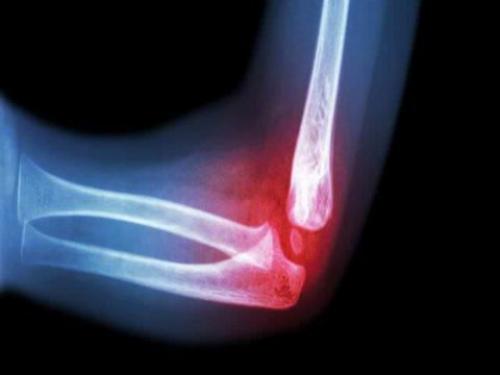

Травмы локтевого сустава при падении. Клиническая картина

Главным симптомом ушиба локтя при падении является сильно выраженный болевой синдром. Он зачастую приводит к болевому шоку, если пациенту сразу не предоставить первую помощь. На проявление признаков травмы будут оказывать влияние:

При ушибах всегда диагностируется гемартроз. Его клиническим симптомом считается резкая боль. После травмы происходит сглаживание контуров локтевого сустава и увеличение окружности сустава по сравнению со здоровой рукой. Пострадавшая конечность занимает вынужденное положение, так как локоть может быть согнут под углом 110-120°. Все движения затруднены и болезненны. При ушибе локтя, когда перелома нет, диагностируется выбухание капсулы в районе щели плечелучевого сустава.

Если у пациента диагностируют ушиб локтя с характерными симптомами, он нуждается в обязательном осмотре травматологом. Так как такая травма может сопровождаться переломом или вывихом. Особенно должно насторожить нарушение чувствительности в кисти, так как это может свидетельствовать о более серьезном повреждении.

Очень часто после травмы отмечается изменение температуры кожных покровов в месте ушиба - локоть становится припухшим и горячим. Пациент жалуется на усиление болезненных ощущений при любом движении или попытке согнуть руку. Может наблюдаться проявление пульсации в месте повреждения или в кисти. В случае диагностирования перелома и ушиба локтя может появиться нарушение подвижности в пальцах травмированной конечности.

Если ушиб был сильный, и у пострадавшего есть такие признаки повреждения как нестерпимая боль, отек локтя, посинение кожных покровов и сильное увеличение локтевого сустава в размерах, пациенту рекомендуется посетить травмпункт и проконсультироваться с травматологом. Врач объяснит, чем лечить сильный ушиб локтя.

Кроме того, есть опасность того, что ушиб может сопровождаться переломом. В травматологическом отделении пострадавшему сделают рентген, чтобы исключить более серьезную травму, чем просто ушиб. Пациенту также предложат лечение ушиба локтевого сустава, которое не следует игнорировать. Такая травма может серьезно повлиять на трудоспособность пострадавшего.